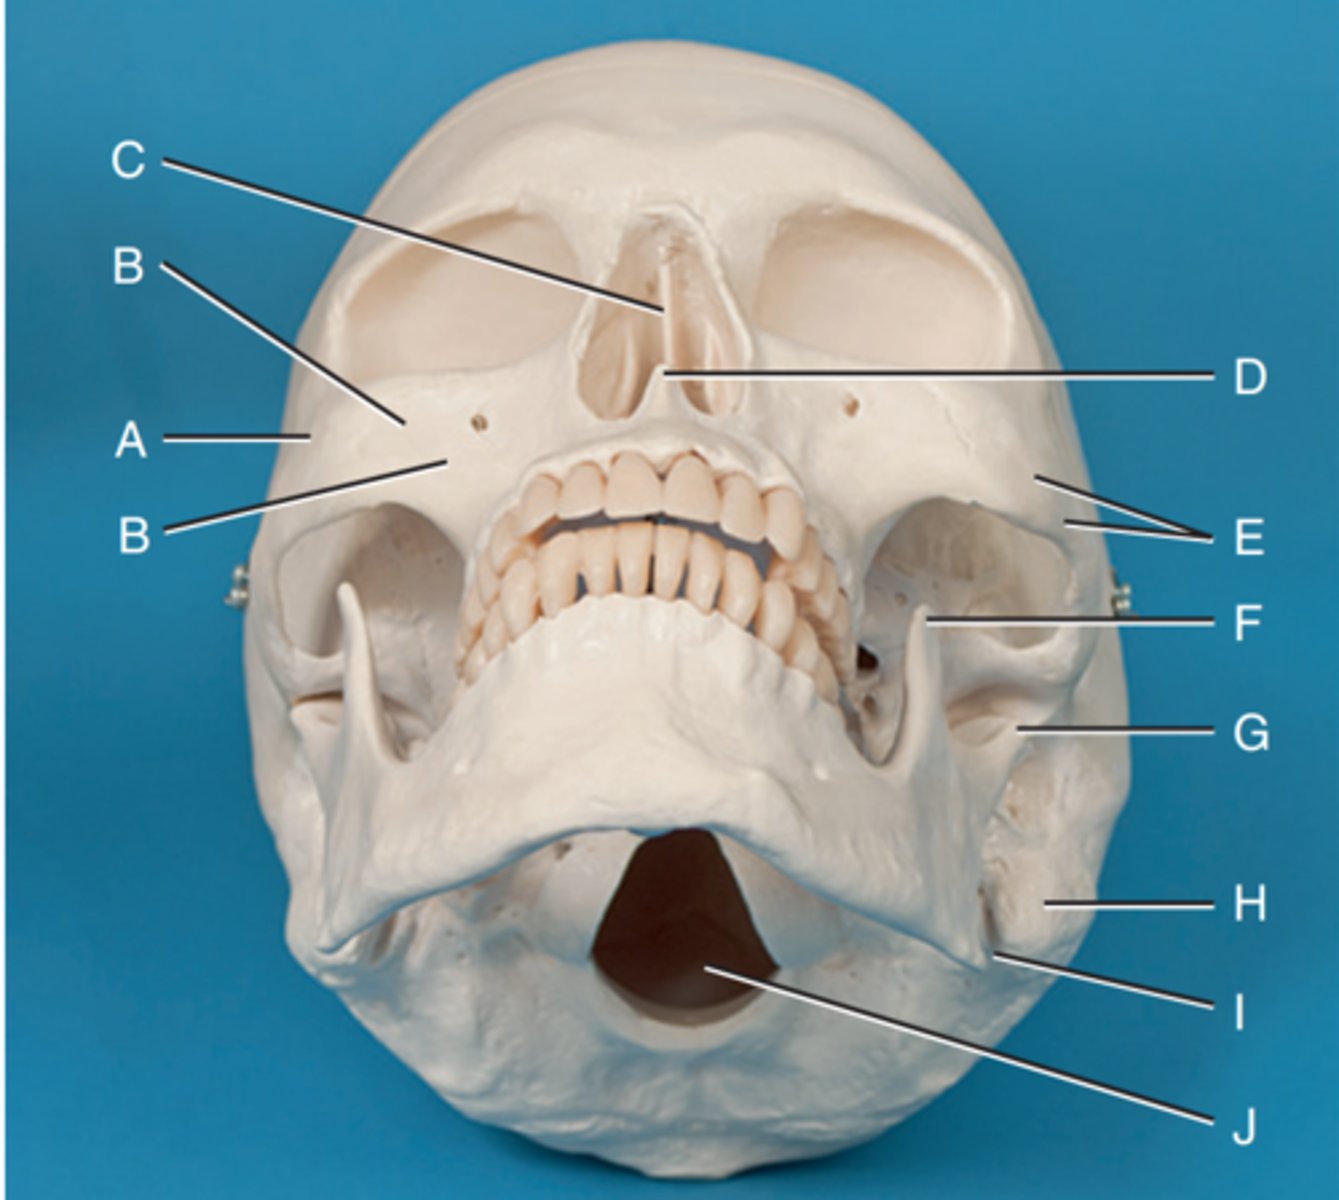

Zygomatic prominence

Label A

Body of maxilla

Label B

Bony nasal septum

Label C

Anterior nasal spine

Label D

Zygomatic arch

Label E

Coronoid process

Label F

Condyle

Label G

Mastoid process of temporal bone

Label H

Angle of mandible

Label I

Foramen magnum

Label J